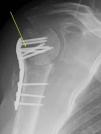

DiagnósticoOsteomielitis humeral proximal grado IV B de Cierny-Mader4, por Staphylococcus coagulasa negativo. El antibiograma indicaba sensibilidad a penicilina, cefotaxima, eritromicina, tetraciclina, levofloxacino, vancomicina y cotrimoxazol. Hipercaptación gammagráfica (fig. 2).

EvoluciónDado el agente patogénico, clínica y aumento de velocidad de sedimentación globular (VSG: 140mm/h), retiramos el material y colocamos un espaciador cementado con gentamicina (fig. 3). Se instaura posquirúrgicamente clindamicina por vía intravenosa (i.v.). El paciente estuvo los 3 primeros meses posquirúrgicos con antibioterapia por vía oral (v.o.): levofloxacino 500mg 1/24h v.o. y rifampicina 600mg 1/24h v.o. (considerando la sensibilidad del patógeno y la alergia del paciente a la penicilina). A los 6 meses desde la intervención la infección se controla (VSG: 17mm/h), con arco de 100° (flexión anterior/abducción activas). El paciente rehusó retirarse el espaciador. Al año posquirúrgico, la infección sigue controlada, con arco similar.